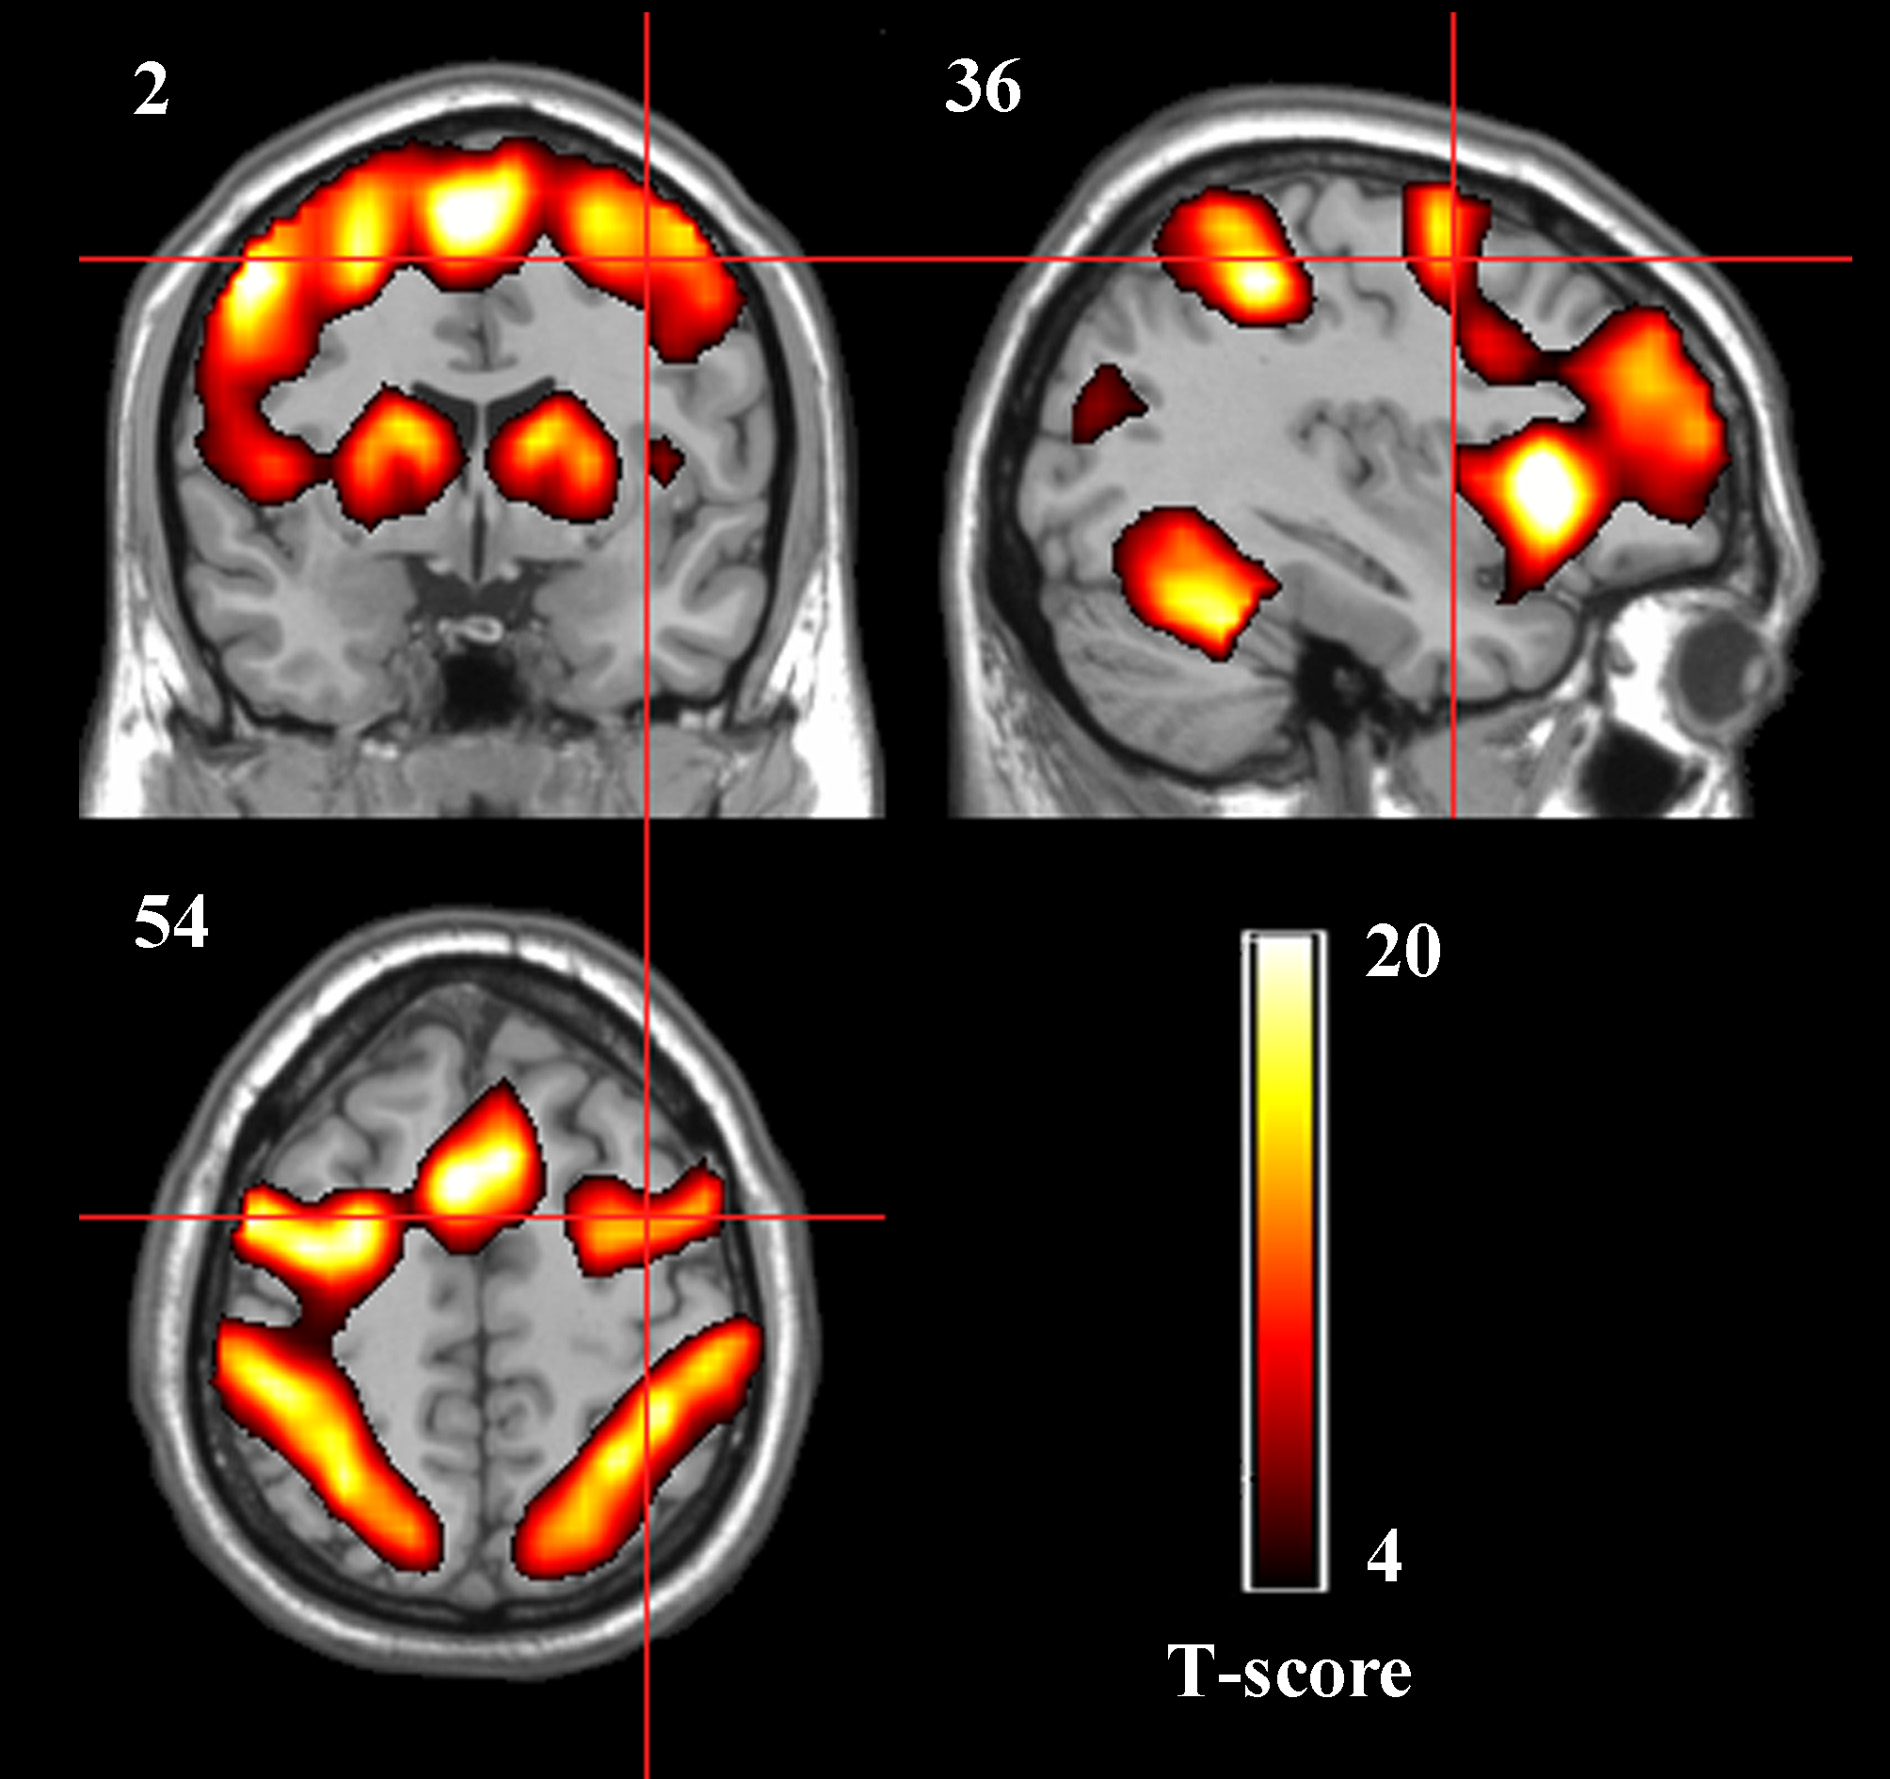

The spatial activation patterns across the four rtfMRI training sessions in the two groups displayed stability and consistency, including the bilateral dPMA, SMA, contralateral M1, SPL, BG, and cerebellum. Whole-brain analysis showed that there was no significant difference between TrainD and TrainA both in the experiment group and in the control group, and only significant difference between TrainC and TrainD in the experiment group, which contained increased activation in the target region, as well as part of the left dPMA and SMA (paired t-test, p<0.001, cluster>10, uncorrected) in TrainD. According to these results, nine ROIs were selected: left dPMA, right dPMA, SMA, left M1, cerebellum, left SPL, right SPL, left BG and right BG (Figure 3).

Figure 3

Group activation maps of the two groups together during the rtfMRI imagery training (p < 0.05, cluster size > 41, FDR correction). The peak value in the right dPMA was located at the MNI coordinates x = 39, y = −1, z = 42.